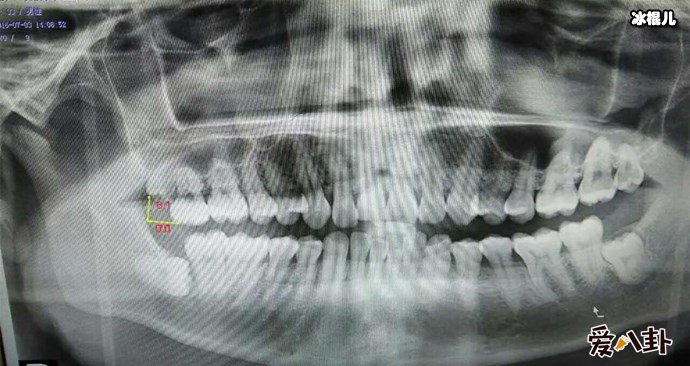

X光下的智齿

不少人都被智齿折磨的痛不欲生,所以么长智齿疼又应该怎么办呢,有这么一个小窍门,如果疼的时候可以含点冰块缓解疼痛,或者用冰块在脸部外敷,一般平时在饮食上要注意,吃的太辛辣就会加重疼痛感,而且每天都要注意清洗口腔,避免口腔滋生细菌,导致长智齿的部位发生感染,一般来说长智齿了就应该马上去医院处理拔掉它,不然智齿压迫了神经,不处理就会遭受长期的疼痛折磨还有进一步加重